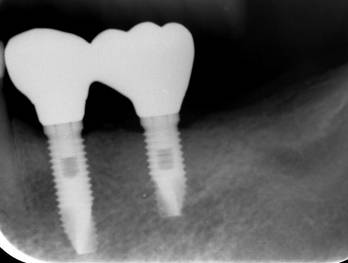

ストローマンインプラントとスプラインインプラント

術前

ストローマンインプラントとスプラインインプラントが隣り合わせに埋入されています.このころストローマンからスプラインに変えています。変えた理由は前歯部の審美性に優れていること、アバットメントの自由度があること、抜歯後すぐに埋入できるなどでした。

6年後。犬歯にコンポジット充填。第一大臼歯はメタルボンドになりました

8年後ほとんど変化がありません

8年後メタルボンド、反対側はジルコニアクラウン

12年後